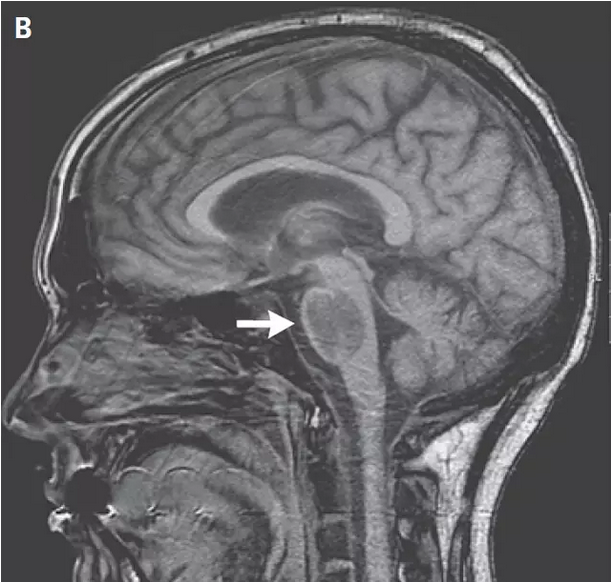

图1. 脑桥右侧份出血后改变